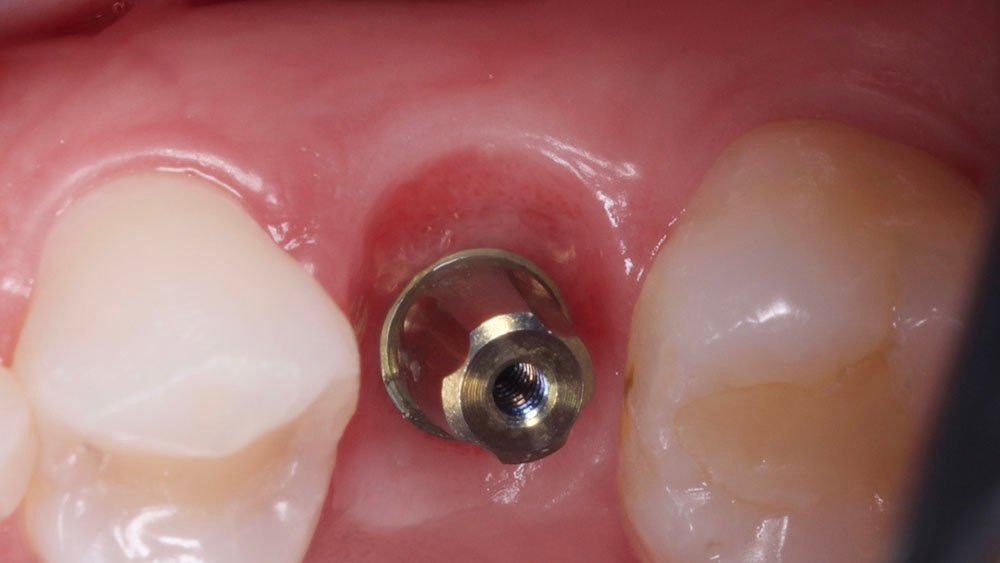

Confeccionou-se um dente provisório aparafusado com coifa de titânio 4,5 x 4 mm – Linha Ideale (Implacil De Bortoli, São Paulo-Brasil), sobre o Pilar Ideale 4,5 x 4 x 2,5 (Implacil De Bortoli, São Paulo-Brasil), apoiado no Implante Maestro 4 x 11 (Implacil De Bortoli, São Paulo-Brasil), obtendo um torque aproximado de 40N. E por fim, realizou-se a proservação e acompanhamento radiográfico.

No acompanhamento mensal realizou-se proservação e radiografias periapicais da região para verificar a cicatrização dos tecidos e integridade do implante. Após o período de três meses, foi cimentada uma coroa definitiva de zircônia monolítica.